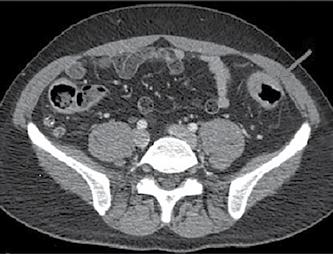

În iulie 2018, pacientul a revenit la control, normoponderal (IMC 20,6 kg/ m2), fiind în remisiune clinică, iar bi ologic în limite normale. S-a efectuat o reevaluare colonoscopică la care s-au identificat pseudopolipi și leziuni cica triceale postinflamatorii la nivelul între gului colon, iar la 25 cm de orificiul anal, un ulcer cu diametrul de 20 mm (Figura 1), din care s-au prelevat multiple biopsii. Aspectul histologic a relevat adenocar cinom colonic moderat diferențiat. La examinarea CT toraco-abdomino-pelvin, s-au vizualizat micronoduli pulmonari nespecifici, o îngroșare parietală la ni velul ceco-ascendentului cu aspect infla mator și o îngroșare parietală asimetrică la nivelul joncțiunii recto-sigmoidiene, sugestivă pentru un substrat tumoral (Fi gura 2).

Figura 1. Leziune decelată colonoscopic la 25 cm de OA Figura 2: Îngroșare parietală asimetrică la nivelul joncțiunii recto-sigmoidiene Figura 3. Adenocarcinom moderat diferențiat, cu arhitectură tubulară